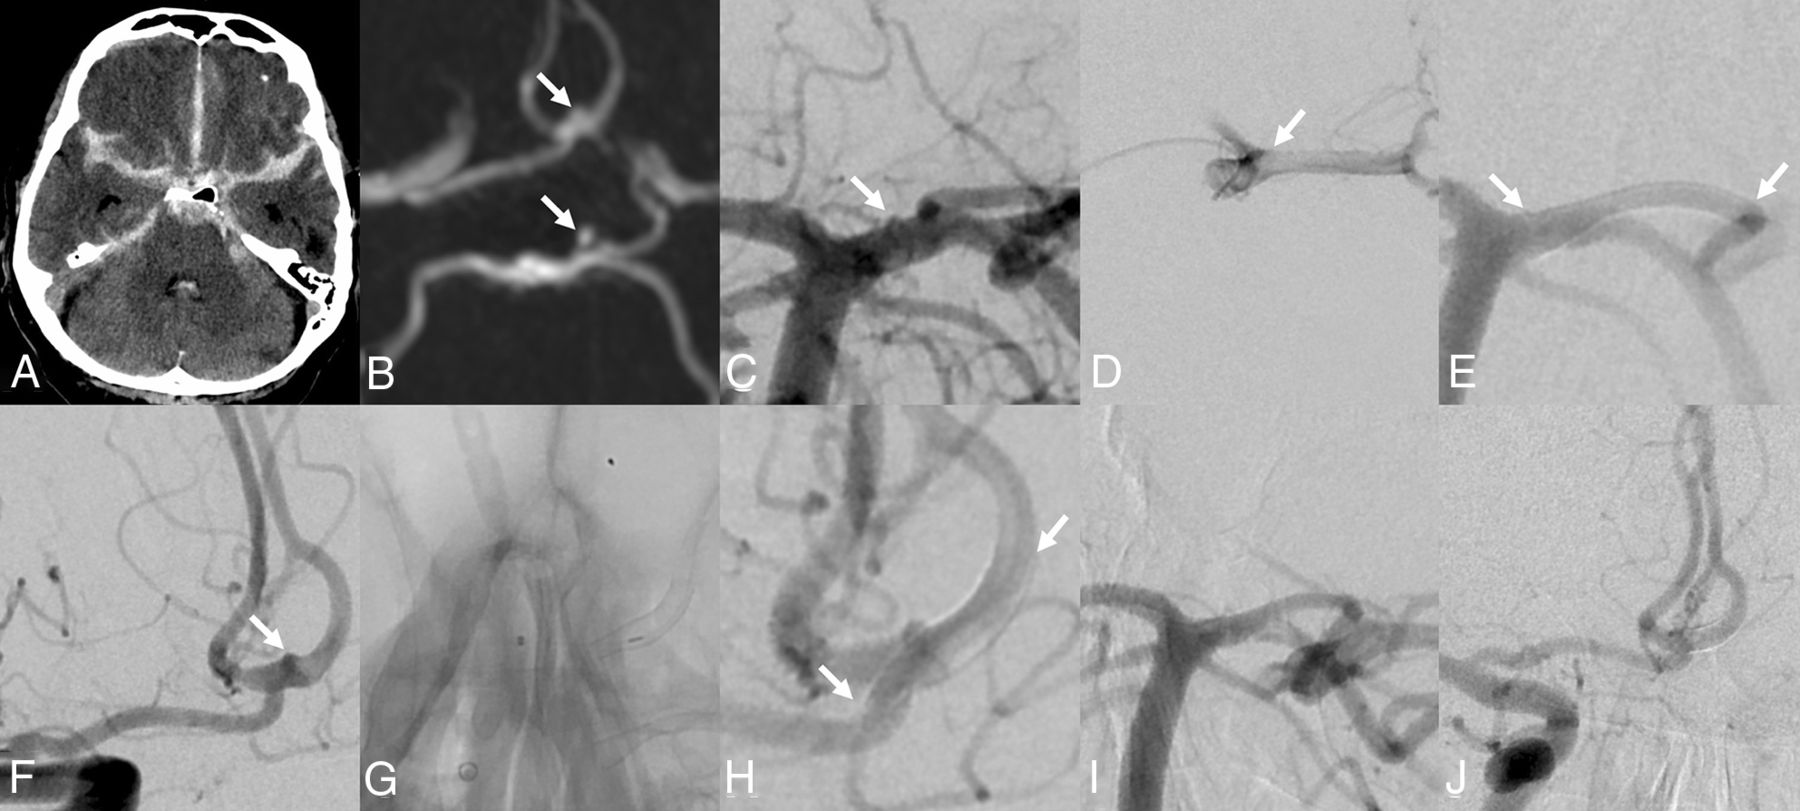

A, Initial NCCT showing the SAH. B, Axial MIP of the MRA. The suspected intracranial aneurysm of the anterior communicating artery (AcomA) and the posterior communicating artery (PcomA)/P1 can be seen (white arrows). C, DSA from the treatment. Left vertebral artery injection; a detailed view of the basilar artery head is shown. The blood-blister-like aneurysm of the P1 segment of the left posterior cerebral artery with the PcomA is demonstrated (white arrow), corresponding to the MRA, though smaller-appearing. D, Microcatheter injection. The tip of the microcatheter is in the distal left ICA, coming from the posterior via the PcomA. The left carotid-bifurcation is demonstrated (arrow). E, DSA after flow-diverter placement, reaching from the beginning of the P1 segment of the left posterior cerebral artery to the left PcomA, covering the left P1/PcomA angle (arrows pointing to the ends of the flow diverter). The aneurysm is no longer seen. F, Right ICA injection. The blood-blister-like aneurysm on the AcomA is identified, corresponding to the MRA. G, Unsubtracted view right after the deployment of the flow diverter from the A2 segment of the left anterior cerebral artery into the A1 segment of the right anterior cerebral artery. The delivering wire and the microcatheter are still in place. H, DSA after flow-diverter detachment. The aneurysm is covered but still filling with contrast (arrows indicate the ends of the flow diverter). I, Control angiogram left vertebral artery injection. The P1/PcomA aneurysm is occluded; the flow diverter is patent. J, Control angiogram of the right common carotid artery injection. The AcomA aneurysm is closed. The flow diverter is patent but shows a proximal shortening into the left A2 segment, just covering the site of the aneurysm (this is patient 1, Online Supplemental Data).